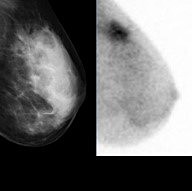

• Molecular Breast Imaging

Molecular Breast Imaging

Michael K. O'Connor, with the help of Deborah J. Rhodes, came up with Molecular Breast Imaging. It is kind of like a mammogram but it is mainly to find tumors in the breast. In a normal mammogram it highlights dense breast tissue and tumors. So this device will help distinguish dense breast tissue from a tumor. It helps women around the world get correct results and find the tumor a lot quicker.